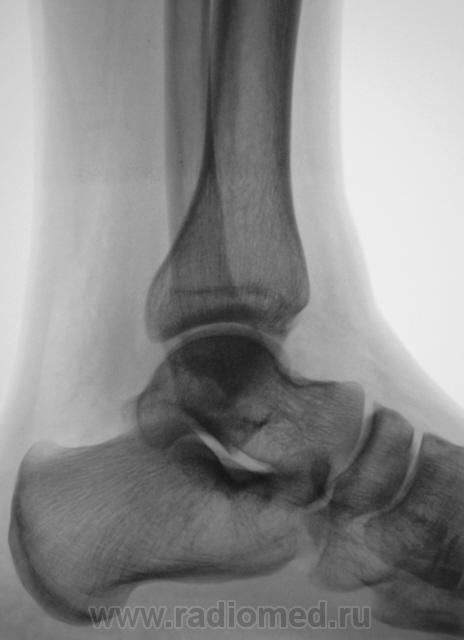

Травма. Пациент направлен на рентгенографию голеностопного сустава.

перелом обеих лодыжек и переднего отдела пяточной кости

Согласен кроме пяточной кости. Там - N.

Если, в пяточной кости "норма", то, что тогда, помеченное стрелками?